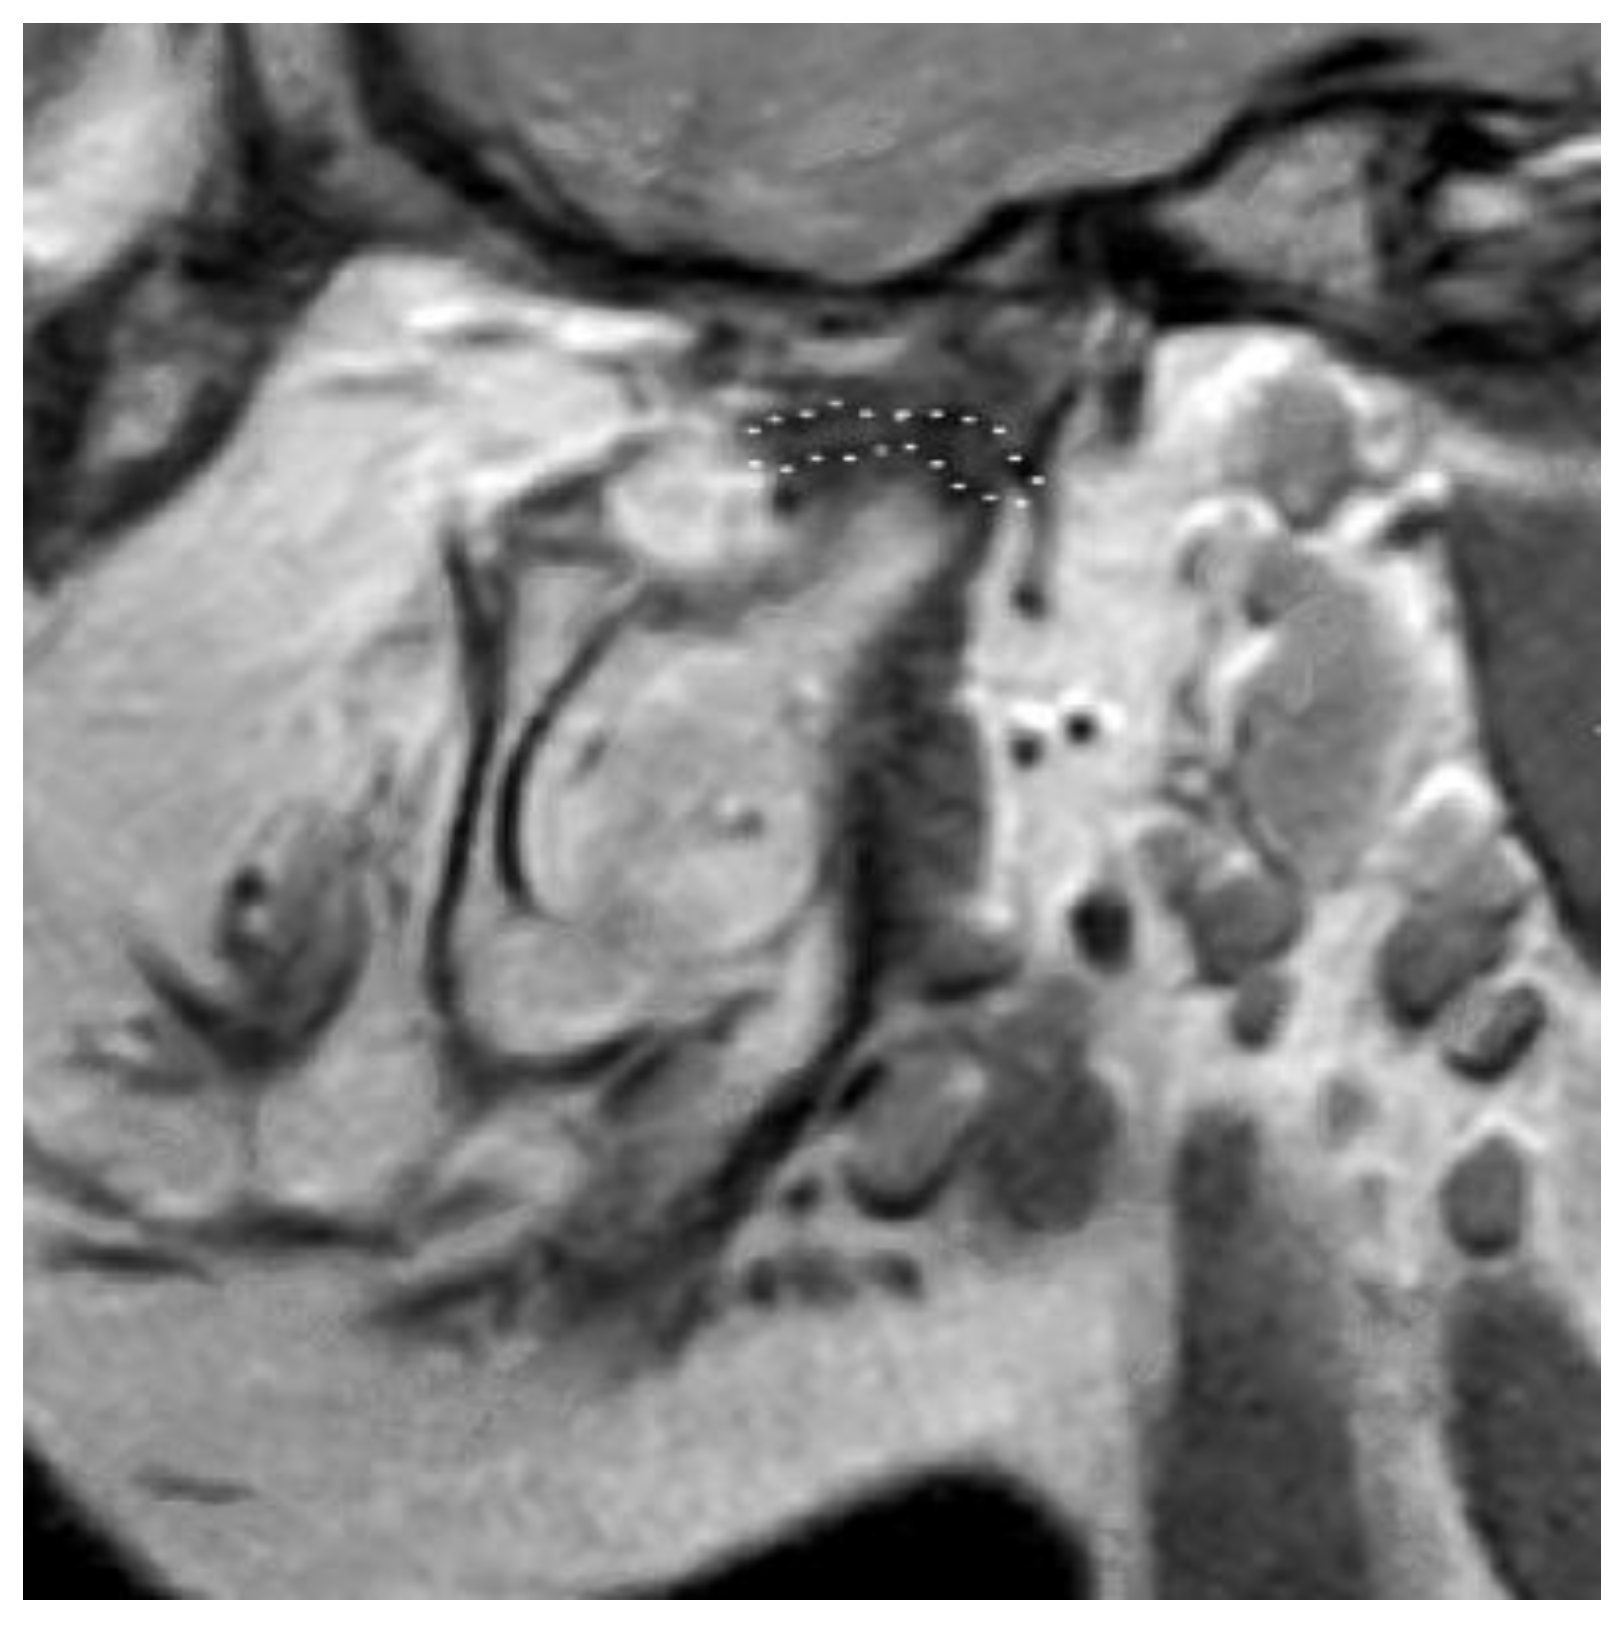

3.2. Definition of Disc Classification